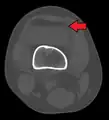

Lipohemarthrosis (presence of fat and blood from bone marrow in the joint space after an intraarticular fracture) seen on X-ray in a person with a subtle tibial plateau fracture

Lipohemarthrosis due to a tibial plateau fracture